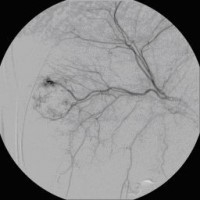

Superselektive transarterielle Chemoembolisation (TACE) mit Sondierung eines tumorversorgenden Gefäßes 1

(Bild 3 von 5)

Superselektive transarterielle Chemoembolisation (TACE) mit Sondierung eines tumorversorgenden Gefäßes 1

(Bild 3 von 5)

Superselektive transarterielle Chemoembolisation (TACE) mit Sondierung eines tumorversorgenden Gefäßes 2

(Bild 4 von 5)

Superselektive transarterielle Chemoembolisation (TACE) mit Sondierung eines tumorversorgenden Gefäßes 2

(Bild 4 von 5)

Superselektive transarterielle Chemoembolisation (TACE) mit Sondierung eines tumorversorgenden Gefäßes 3

(Bild 5 von 5)

Superselektive transarterielle Chemoembolisation (TACE) mit Sondierung eines tumorversorgenden Gefäßes 3

(Bild 5 von 5)